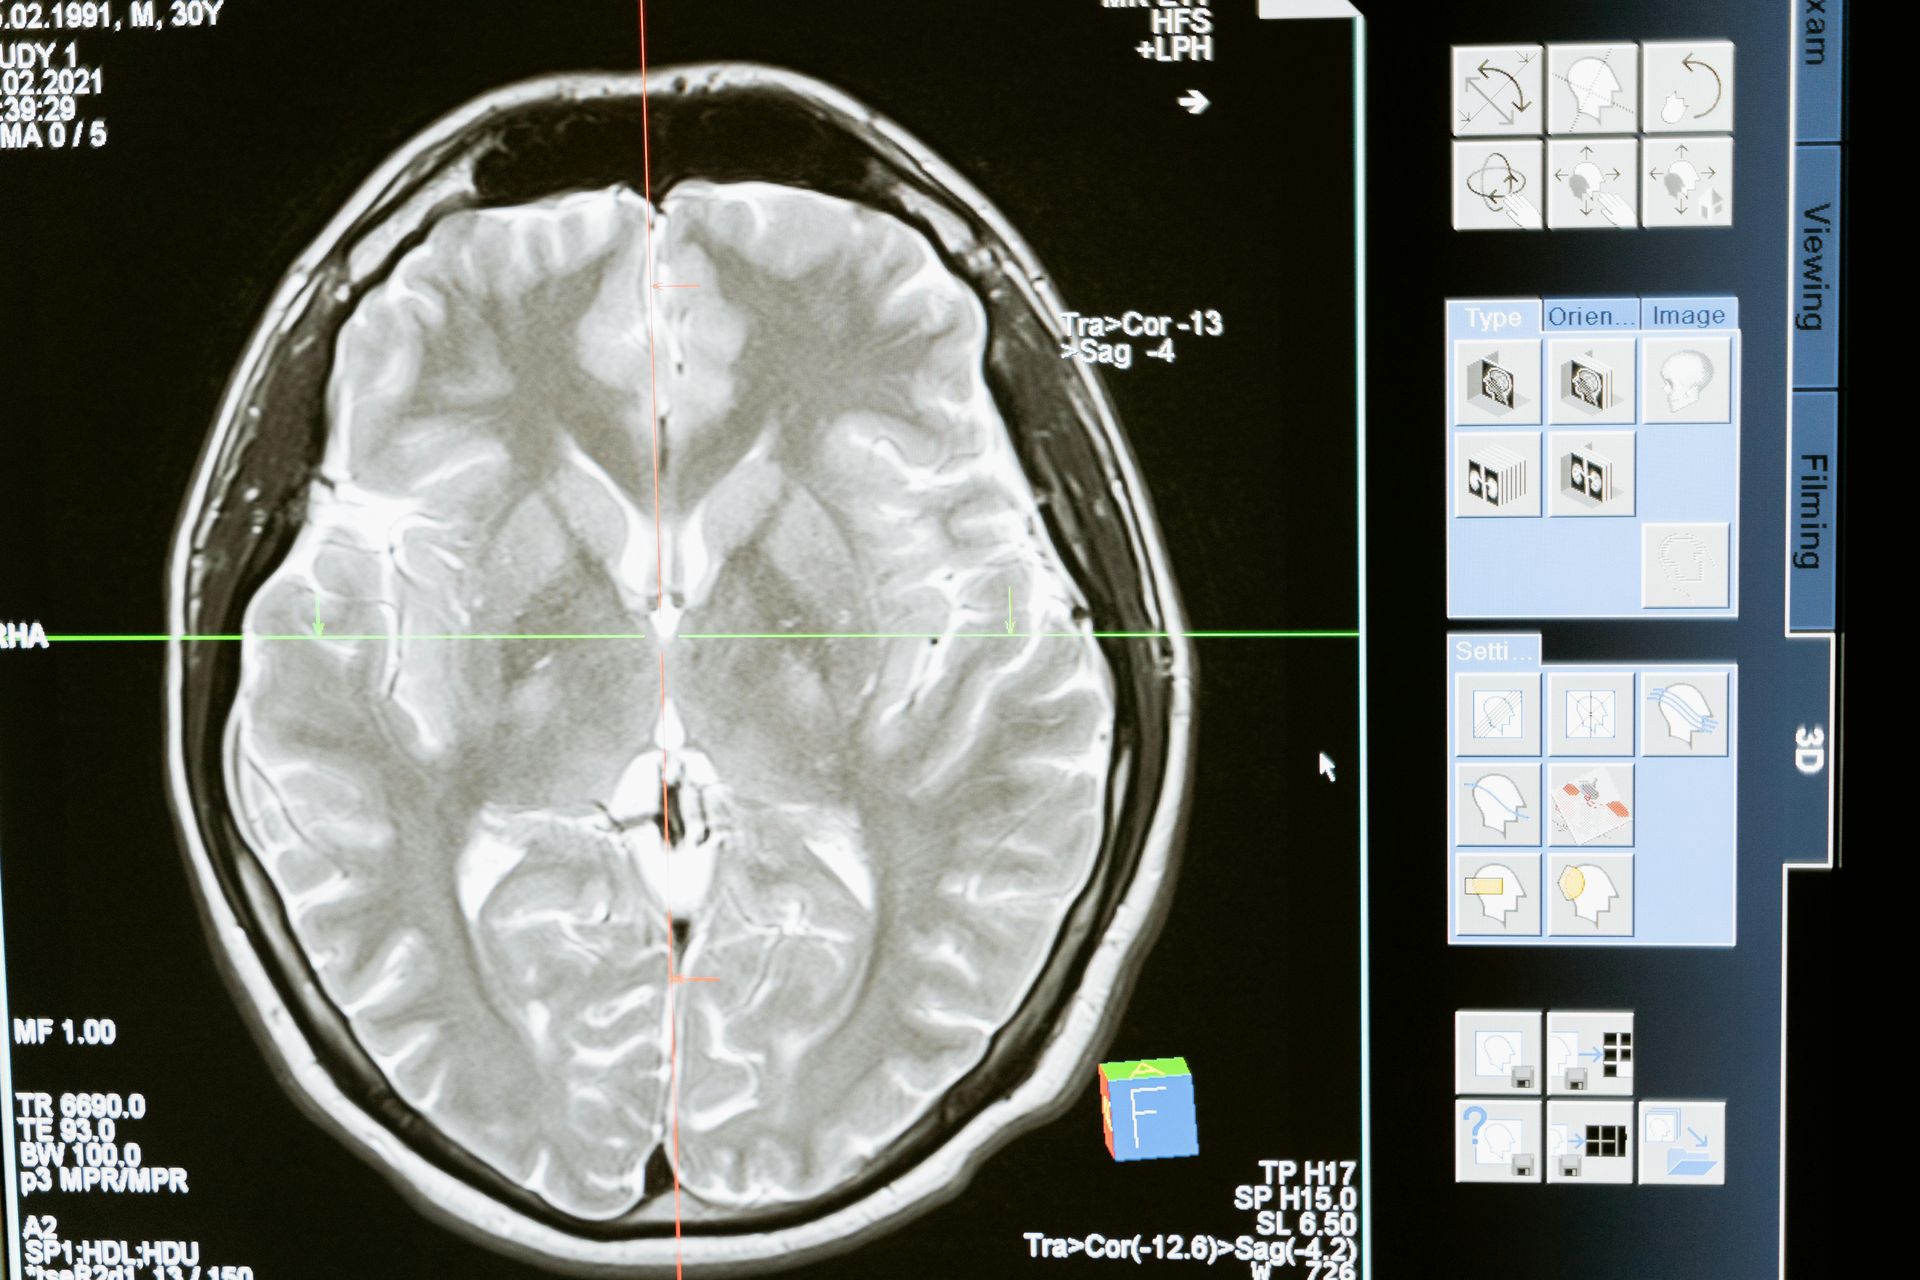

• 12:00 – 13:00: Reviewing CT scans and treatment plans with Oncologists and Medical Physicists.